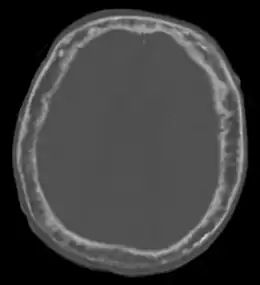

Elle est caractérisée par l'hypertrophie et la déformation de certaines pièces osseuses, principalement le bassin (près des 3/4 des atteintes), le crâne (40 % des atteintes), le rachis lombaire (près de la moitié des atteintes) et les os longs[4]. On peut retrouver des signes vasomoteurs, tels qu'une chaleur, une rougeur de la peau sus-jacente.

Elle peut parfois se compliquer de compressions de structures adjacentes à l'os atteint : surdité par atteinte crânienne, atteintes nerveuses diverses (nerfs crânien, canal lombaire étroit...). La transformation en sarcome, cancer osseux, est rare mais possible.

Le cas Beethoven

Bien que cette hypothèse soit controversée[32], Beethoven pourrait avoir été atteint de la maladie de Paget selon une autopsie faite à Vienne le par Karl Rokitansky qui a décrit une voûte crânienne uniformément dense et épaisse et des nerfs auditifs semblant anormaux[33].

Il souffrait de déformations compatibles avec la maladie osseuse de Paget : sa tête semble avoir continué à grandir à l'âge adulte (à la fin de sa vie, il ne rentrait plus dans son chapeau, ni dans ses chaussures), son front est devenu proéminent, sa mâchoire était grande et son menton saillant. Il est possible et probable qu'une compression de certains nerfs crâniens, notamment le nerf auditif (huitième nerf crânien) ait affecté son ouïe. C'est l'une des hypothèses rétrospectivement apportée pour expliquer son humeur et sa surdité (qui a débuté vers 28 ans et était totale à 44 ans)[33] ; l'autre, qui n'est pas exclusive de la première, étant le saturnisme, sur la base de mesures du plomb contenu dans des mèches de cheveux qui ont été conservées. Ce serait cependant une cirrhose du foie d'origine alcoolique qui l'aurait tué.